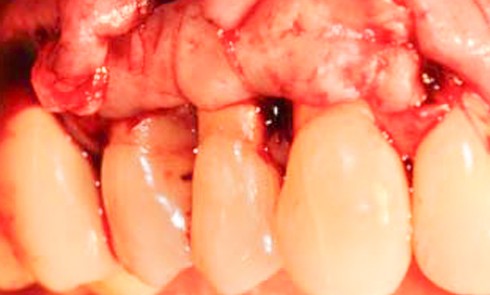

Un rapport de consensus publié en 2022 [1] a formulé des conclusions concernant les facteurs susceptibles d’influencer les déhiscences de tissus mous péri-implantaires. Parmi les facteurs de risque identifiés, nous pouvons citer une angulation trop vestibulaire lors du positionnement implantaire et un phénotype péri-implantaire fin.

La greffe de tissu conjonctif est considérée comme un facteur protecteur contre l’apparition d’une déhiscence péri-implantaire.

Enfin, deux facteurs qui avaient été jusqu’à présent suggérés comme des facteurs de risque ont été écartés et ne montrent aucune implication significative, à savoir : l’implantation immédiate et l’épaisseur d’os vestibulaire.